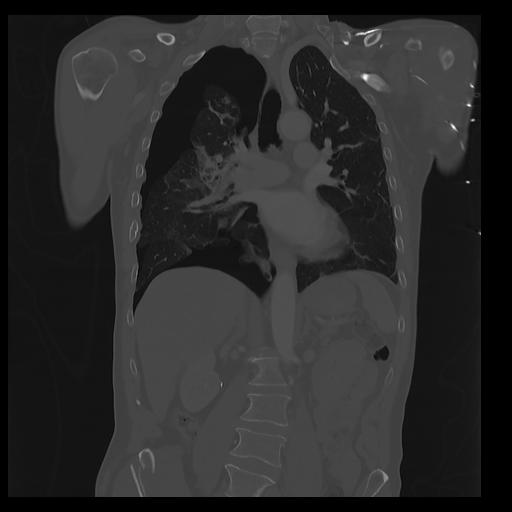

32 PULMON,CE,Coronal,3.000,PULMON,Coronal,